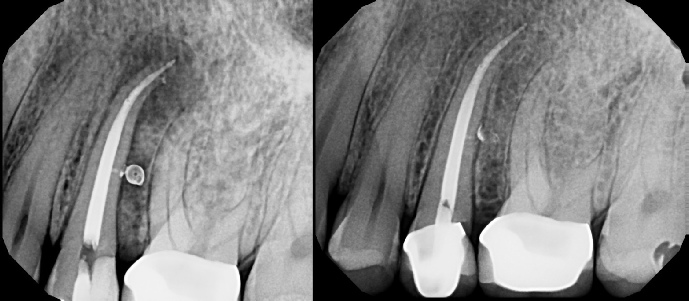

COMPLICATED ANATOMY LARGE LESIONS CALCIFIED CANALS PERFORATION / RESORPTION SEPARATED INSTRUMENTS SURGICAL CASES RETREATMENT / pOST REMOVAL OPEN APICES ACCESS THRU CROWNS Root Canal Case Portfolio

Pre-op Post-op 6 mos.